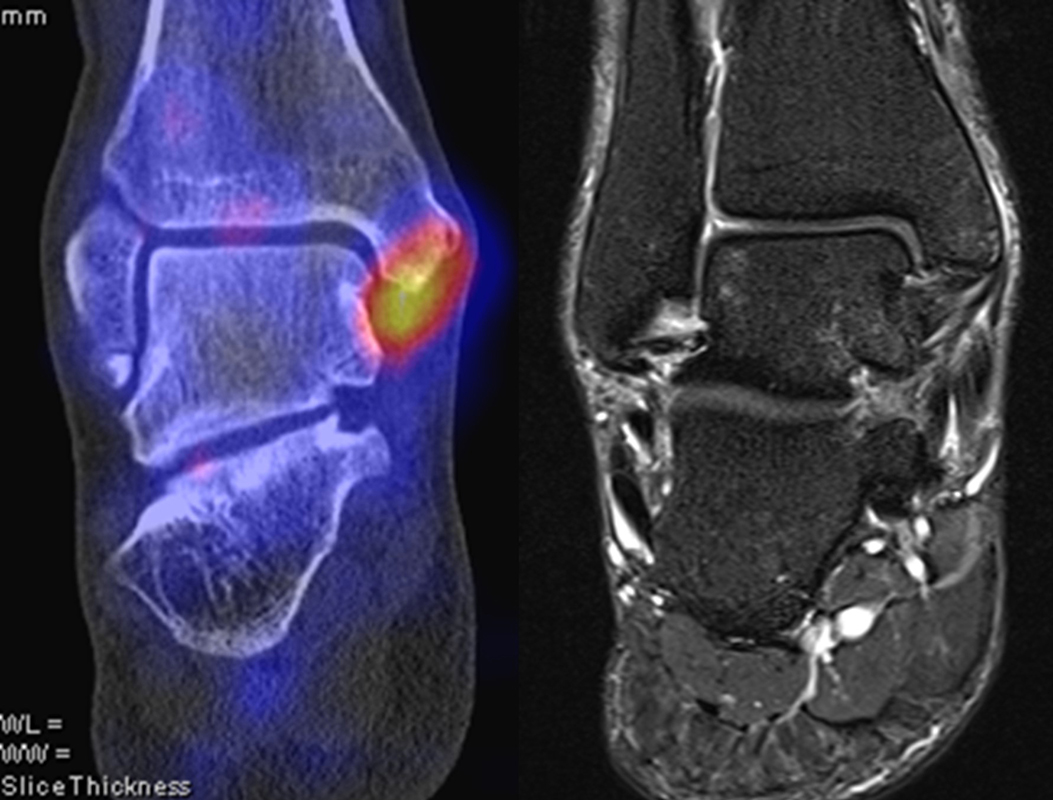

Abbildung 2.2.

Bilder eines Patienten mit Z. n. mehrfachen Sprunggelenksdistorsionen in der Vergangenheit, besonders heftige Distorsion des linken Sprunggelenkes 5 Wochen vor der Untersuchung. Die SPECT/CT zeigt eine instabile osteochondrale Läsion mit deutlicher Aktivierung.